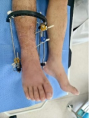

術(shù)后1天復(fù)查X線示:骨折位線良好,關(guān)節(jié)面形態(tài)良好,關(guān)節(jié)間隙正常。外固定架位置適宜。骨折愈合的臨床標(biāo)準(zhǔn):局部無壓痛,無縱向叩擊痛。局部無異?;顒?;X線顯示骨折線模糊,有連續(xù)性骨痂通過骨折線。術(shù)后23周復(fù)查患者骨折模糊,拆除跟骨固定針及脛骨固定半針。術(shù)后25周,骨折處基本達(dá)到臨床愈合標(biāo)準(zhǔn),拆除外固定架,患者可以不住柱拐下地負(fù)重鍛煉(見圖2)。

圖2 患者影像及外觀照片